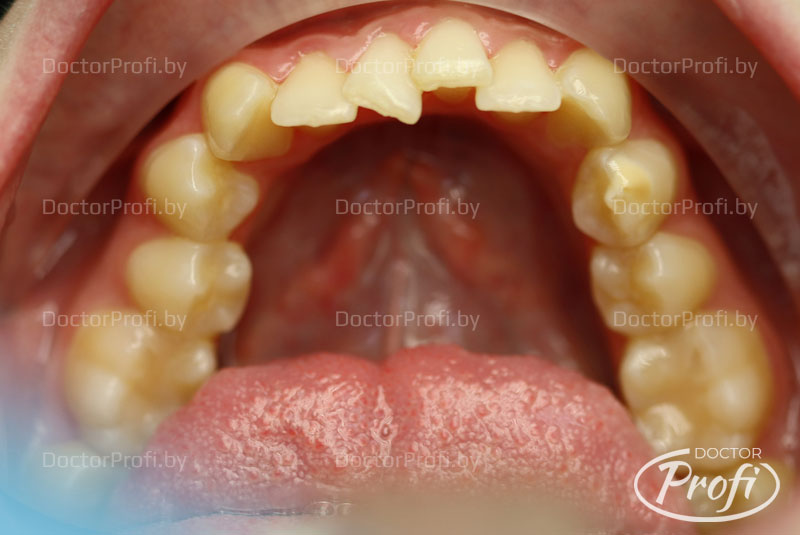

Пациентка обратилась в клинику с жалобами на неэстетичный зубной ряд. Возраст - 21 год. На консультации у ортодонта были выявлены следующие проблемы с прикусом: дистальный прикус, глубокое травмирующее резцовое перекрытие, сужение и укорочение зубных рядов, повороты зубов, скученность, отсутствие зуба 15.

До